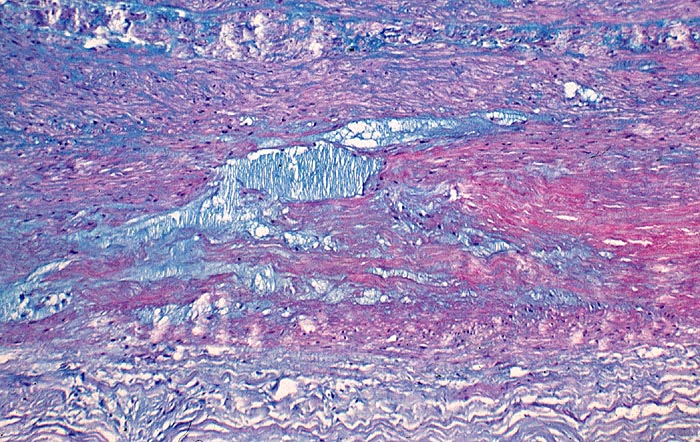

Zystische Mediadegeneration Erdheim Gsell

Aorta abdominalis

Pseudozystische Degeneration der Media. Die zystischen und spaltförmigen Hohlräume sind aufgefüllt mit alcianblauen Mukopolysacchariden.

Besonders häufig kommt die zystische Mediadegeneration beim Marfan Syndrom vor. Sie gilt als wichtiger prädisponierender Faktor für ein Aneurysma dissecans der Aorta.